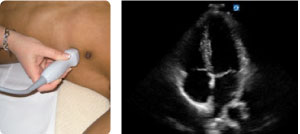

VISTA APICAL 4 CÁMARAS

Identifique todas las cavidades con el transductor dirigido hacia la axila izquierda del paciente manteniendo el marcador de orientación en la posición a las 3. Es la mejor vista para observar el tamaño de la cavidad y las válvulas.